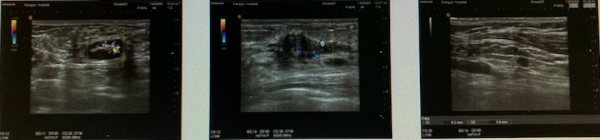

乳腺彩超:左乳12-5點方位,可見散在的結節,較大者29*20*31mm,位於1點方位,形態欠規則,邊界欠清,內光點粗,CDFI:結節內可見豐富血流訊號。左側腋窩探及多個結節,邊界清楚,形態規則,較大者18*8mm,CDFI:結節內血流較豐富(圖1)。